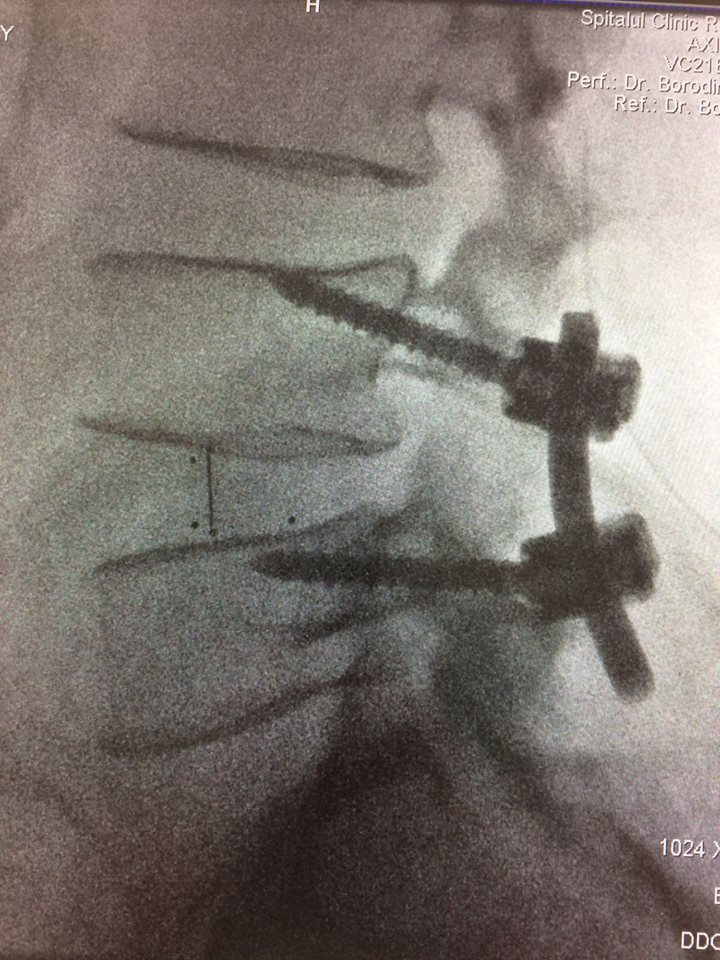

Echipa de specialiști în neurochirurgie spinală a Spitalului Clinic Republican a obținut o nouă realizare. S-a reușit o fuziune intervertebrală cu șuruburi transpediculare și cușcă intervertebrală printr-o incizie mai mică a pielii, de doar 4 cm, recordul anterior fiind de 5 cm. Succesul intervenției se datorează folosirii tehnologiilor moderne (CT intraoperatorie, Neuronavigația spinală, Neuromonitoring intraoperator) și planificării preoperatorii detaliate.

Pentru tratarea unui pacient de 63 ani cu diagnosticul de Spondilolistezis instabil L4-5, însoțit de stenoză de canal lombar, a fost folosit un abord chirurgical nou - Fuziunea Intervertebrală Mediană.

Procedura a început sa fie aplicată în clinică din ianuarie 2016. Până în prezent, folosind tehnica nouă, au fost operați peste 30 de pacienți.